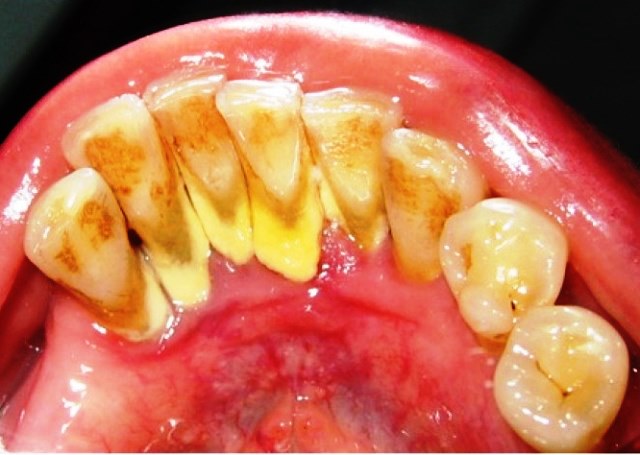

Основная масса зубных паст относится к второй группе — лечебно-профилактических. Их назначением, кроме очищения поверхности зубов, является подавление микрофлоры, которая вызывает кариес и пародонтит, реминерализация зубной эмали, уменьшение воспалительных явлений при заболеваниях пародонта, а также отбеливания зубной эмали.

Выделяют противокариозные пасты, которые содержат кальций и фторосодержащие зубные пасты, а также зубные пасты с противовоспалительным действием и отбеливающие пасты.

Противокариозный эффект обеспечивается присутствием в зубной пасте фторидов (фторид натрия, фторид олова, аминофторид, монофторфосфат), а также кальция (глицерофосфат кальция). Противовоспалительное действие обычно достигается добавлением в зубную пасту экстрактов трав (мята, шавлия, ромашка и др.). Отбеливающие пасты содержат бикарбонат натрия, или соду, которая имеет выраженное абразивное действие. Применять такие пасты каждый день не рекомендуется вследствие риска повреждения эмали. Обычно рекомендуют их применять 1-2 раза в неделю.